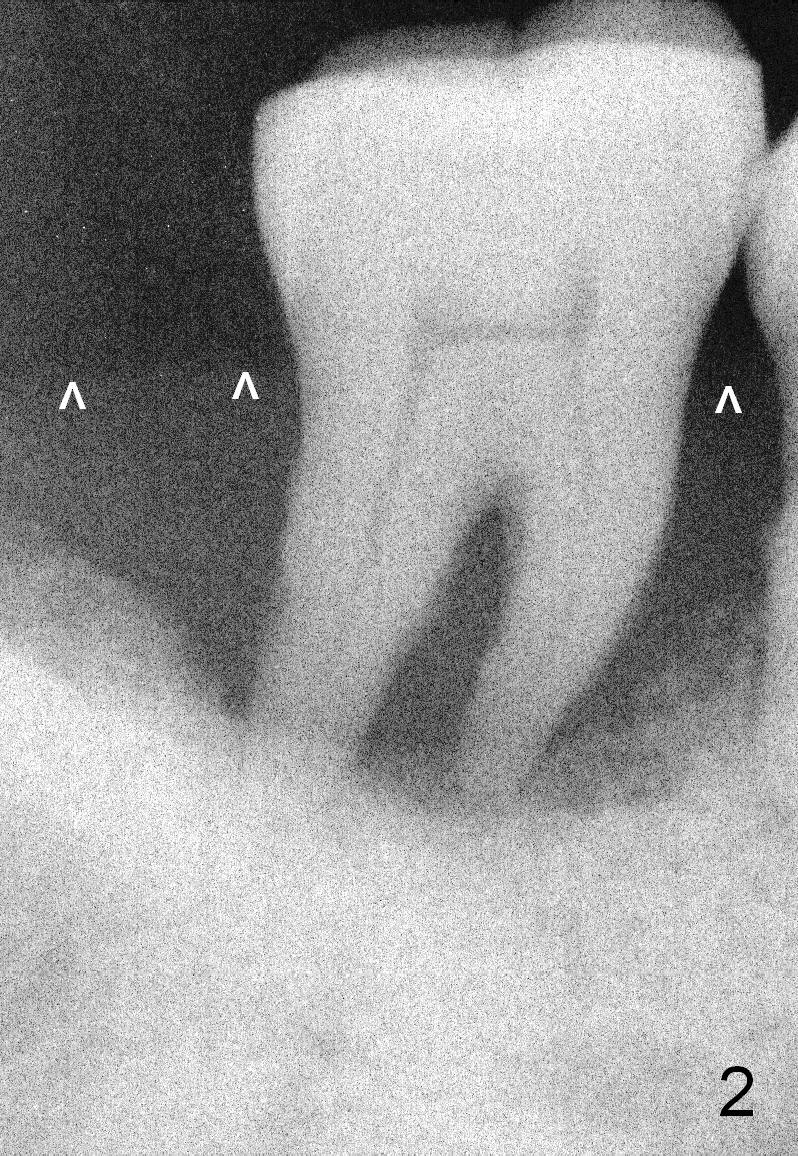

A 46-year-old lady has generalized moderate localized severe (Fig.1 (panorex) #31) chronic periodontitis. Surprisingly there is sufficient bone height (Fig.1 white dashed line: upper border of the Inferior Alveolar Canal). The gingiva is quite thick (Fig.2 (PA) arrowheads: gingival margin). In order to prevent thread exposure associated with immediate implant, a bone-level implant will be placed (Fig.3 5.3x8 mm; green lines) with a long abutment (5.8x5.5 mm (black lines) (6 mm cuff; red lines)). Initial osteotomy depth is between 14 and 17 mm. Insert a parallel pin and take the 1st intraop PA. Use reamers to enlarge osteotomy and collect autogenous bone. A drill with a stopper (5x8mm) will be used prior to placement of the implant mentioned above. Since the opposing is a removable partial denture, an immediate provisional at the site of #31 should be safe to be fabricated. Bone graft will be placed to cover the exposed implant surface. The remaining gap will be filled with collagen dressing and the provisional. A temporary abutment is the other option. The shoulder of the temporary abutment will be subgingival to long extent. Is the plan well executed?